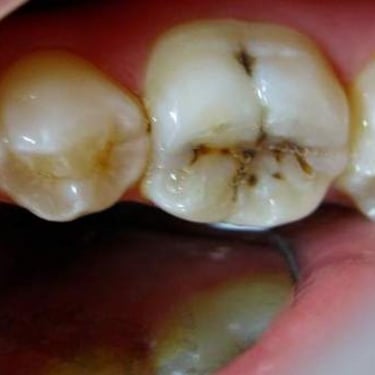

Pulpitis Crónica Hiperplásica

La pulpitis crónica hiperplásica es una inflamación de la pulpa con crecimiento excesivo de tejido pulpar a través de una caries abierta.

Los pacientes notan un tejido rojo que sobresale de la cavidad dental.

El tratamiento incluye la eliminación del tejido afectado y un tratamiento de conducto. Es crucial tratar la caries para evitar infecciones adicionales.